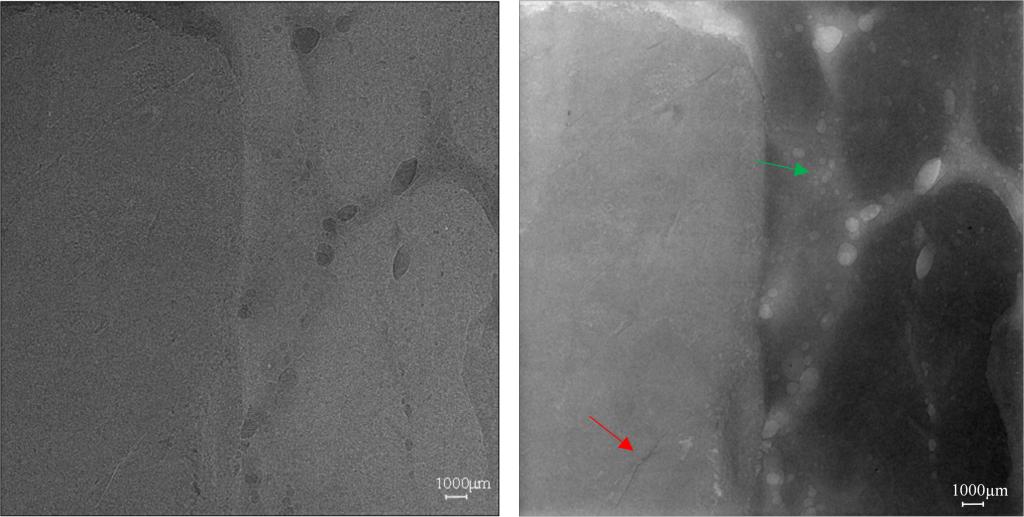

图4 相位信息抽取前后薄层牛肉图像对比